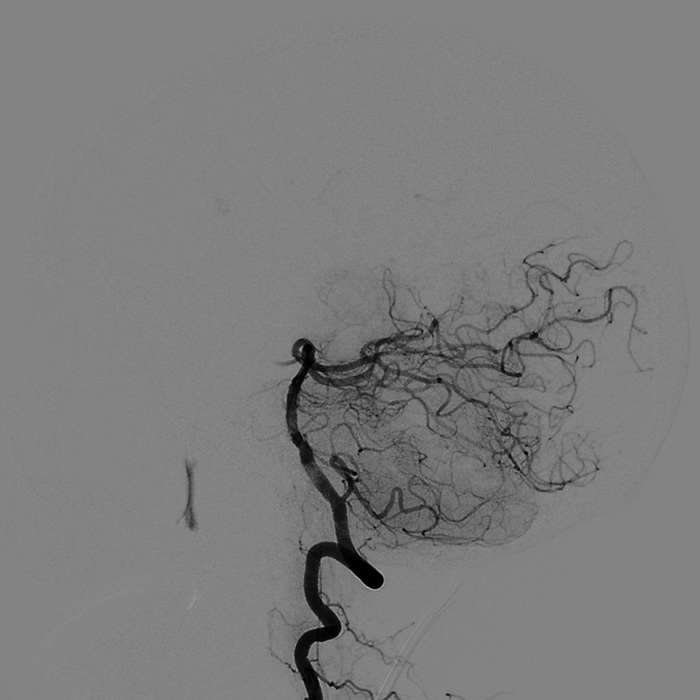

??? 9月3日00:10 ?神經(jīng)外科團隊?wèi){借深厚的介入功底及對顱腦血管病變治療的經(jīng)驗,沉穩(wěn)地將栓子取出,血管恢復(fù)再通,梗塞區(qū)血流灌注隨即恢復(fù)。

取栓后造影顯示雙側(cè)小腦上動脈及雙側(cè)大腦后動脈充盈良好